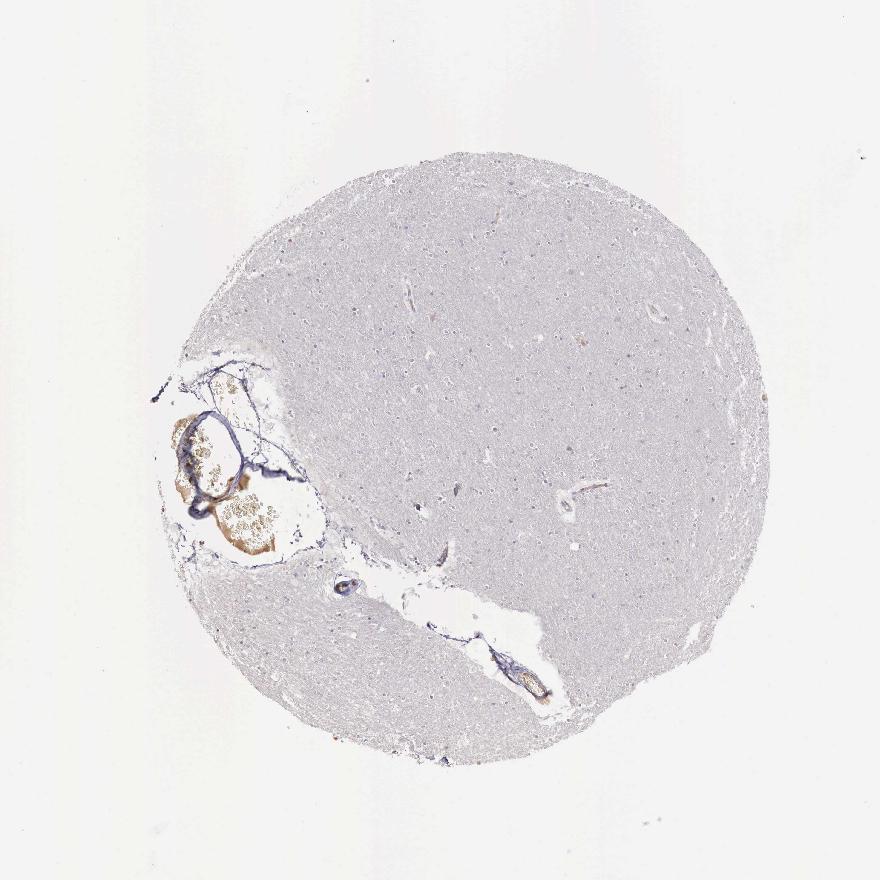

CEREBRAL CORTEX - Antibody stainingi

Antibody staining in the annotated cell types in the current human tissue is reported as not detected, low, medium, or high, based on conventional immunohistochemistry profiling in selected tissues. This score is based on the combination of the staining intensity and fraction of stained cells.

Each image is clickable and will lead to virtual microscopy that enables deeper exploration of all samples and also displays staining intensity scores, fraction scores and subcellular localization as well as patient and tissue information for each sample.

Antibody HPA000339Antibody CAB025136Antibody CAB025269

Endothelial cells LowNot detectedNot detected

Glial cells Not detectedNot detectedNot detected

Neuronal cells LowNot detectedNot detected

Neuropil Not detectedNot detectedNot detected